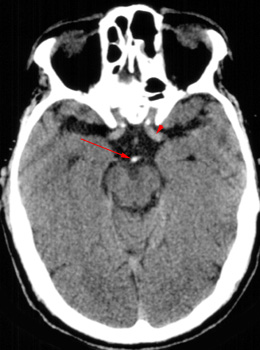

Basilar Thrombosis

Thrombosis

of the basilar artery is a common finding in stroke patients. CT findings

include a dense basilar artery without contrast injection.

Dense basilar artery

(arrow). Compare this to

the normal internal carotid artery (arrowhead). |